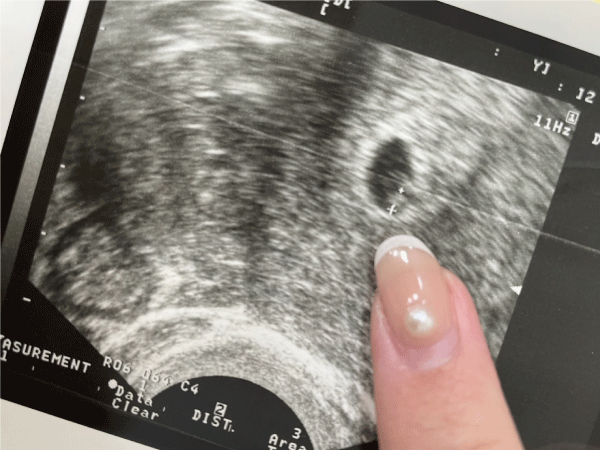

經過艱辛的等待,這一次成功植入了2顆胚胎,在2周後終於驗孕成功